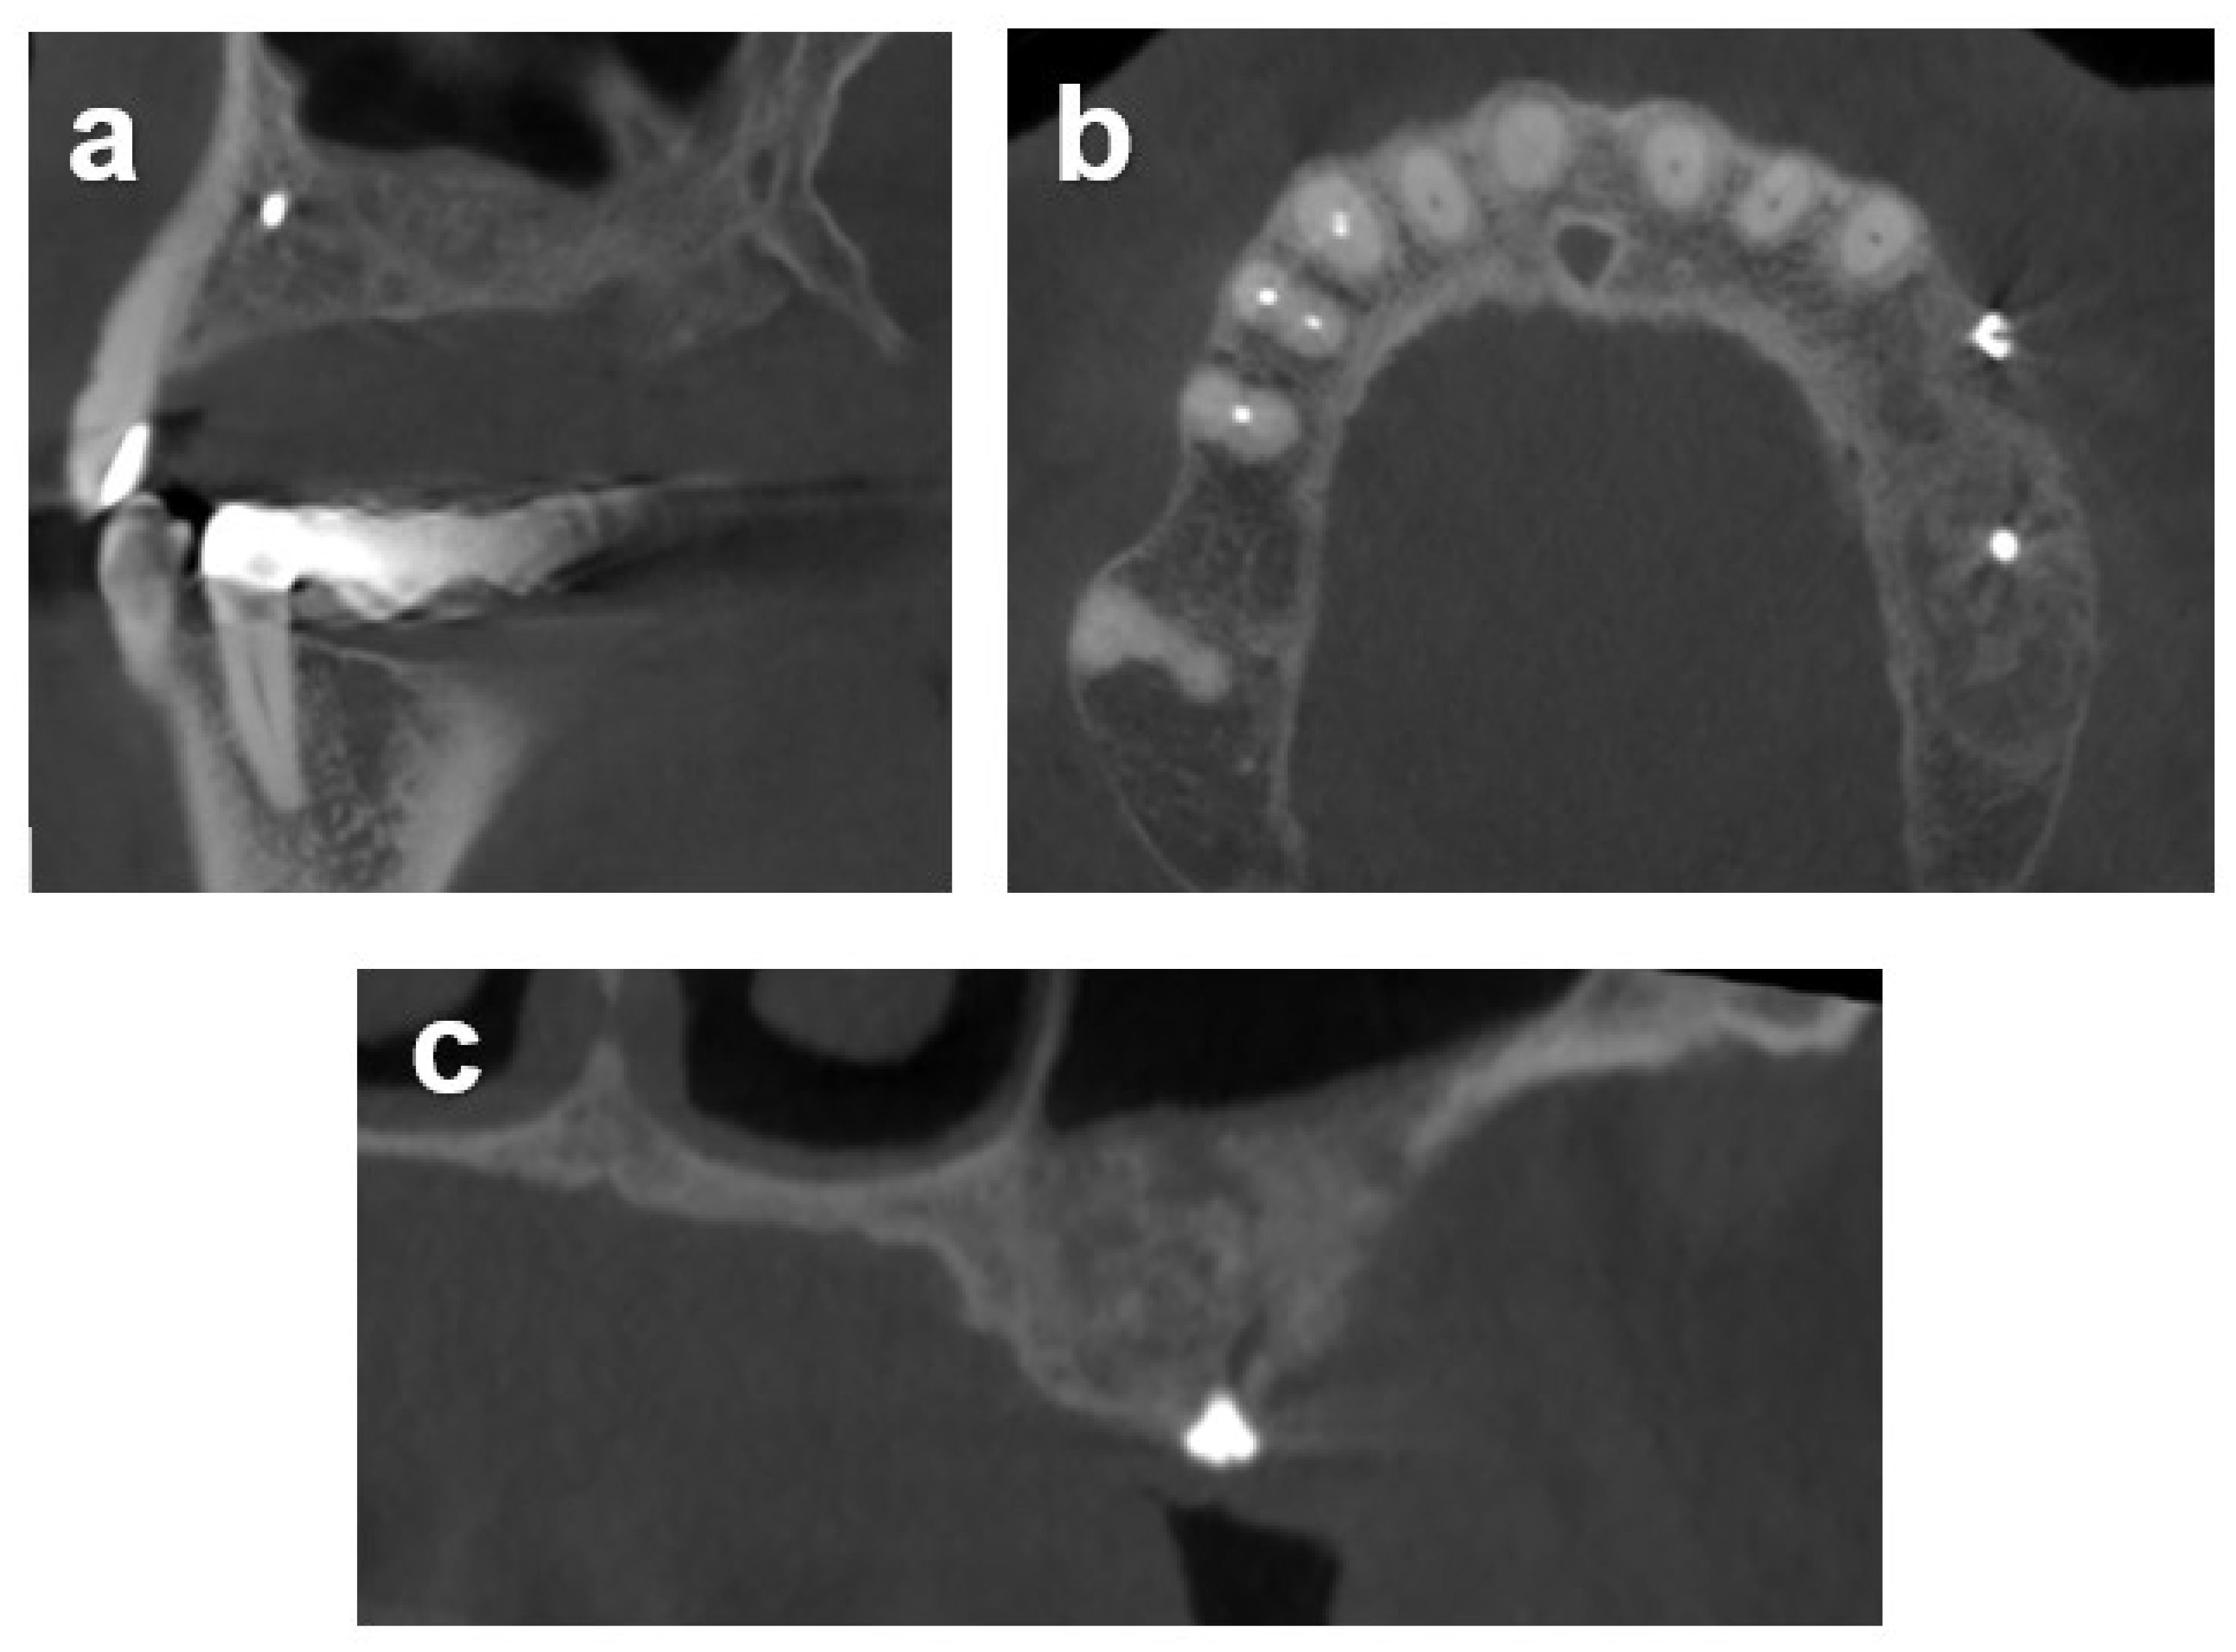

2.7.1. Case 1

2.7.2. Case 2

2.7.3. Case 3

3.2. Radiometric Assessment

| Baseline | 3.0 | 2.0 | 2.0 | 5.0, 8.4 | 3.0 | 3.0 (2.3 to 4.5) | 2.0–8.4 |

| 5-month follow-up | 8.0 | 10 | 11.5 | 12.0, 12.5 | 10 | 10.8 (10 to 11.9) | 8.0–12.5 |

| Horizontal Gain ‡ | 5.0(×9.0) ‡ | 8.0(×9.0) | 9.5(×8.0) | 7.0 (×11.0), 4.0 (×11.0) | 7.0(×5.2) | 7.0 (5.5 to 7.8) | 4.0–9.5 |